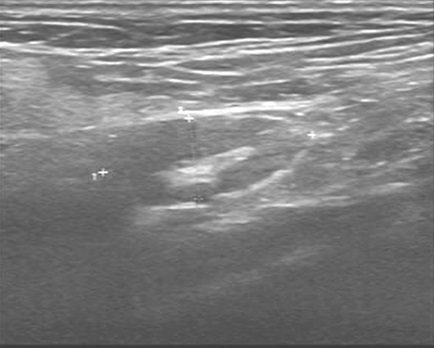

1小时条评论55岁女性,因左下腹反复疼痛2月余,加重1个月就诊。如何诊治? 【病例摘要】 患者,女性,55岁,因左下腹反复疼痛2月余,加重1个月就诊于四川大学华西医院。查体:下腹部触及8cmtimes;7cm包块,质韧,活动性差。 既往史及家族史 无特殊,家族中无类...